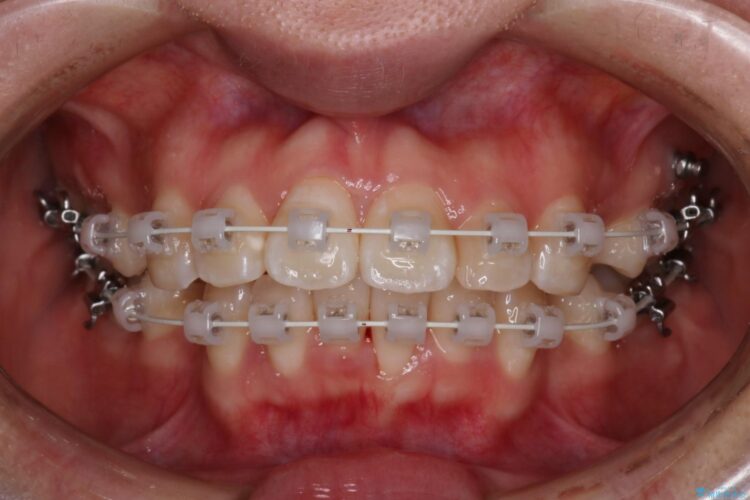

上下4番目の歯を抜歯してガタつきを改善しながら口元を下げる治療計画を立てました。

抜歯矯正で口元を下げたことで、Eラインが大変綺麗になりました。

期間も1年9ヶ月と比較的短期間で治療完了することができました。